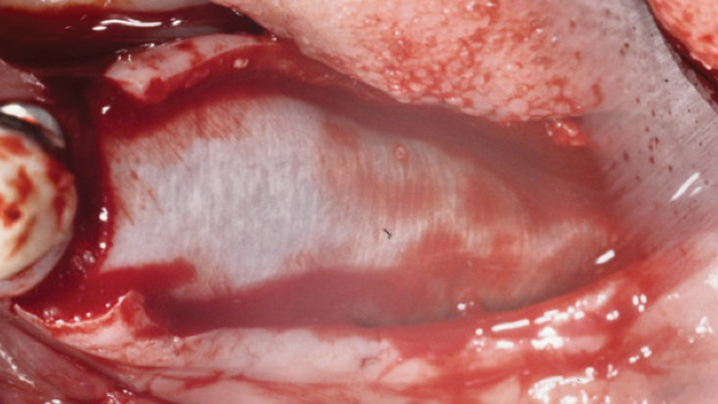

Clinical case: Ridge splitting technique using SmarThor + AnyRidge as expander

- Courtesy of Dr.Kwang-Bum Park, Korea -

Keywords

AnyRidge, ridge splitting, GBR, Dr. Kwang-Bum Park, mandibular posterior, SmartThor, Mega-Oss, thin ridge, bone regeneration

Products:

AnyRidge implant system. SmarThor, Mega-Oss